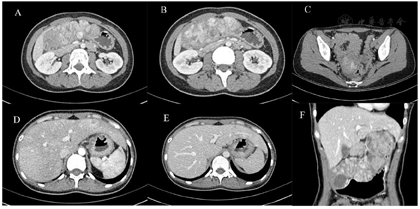

查体:上腹部及右下腹轻度压痛,剑突下可及一约10 cm×6 cm包块,边界不清,无反跳痛或肌紧张。查血:红细胞3.02×1012/L,血红蛋白98g/L,余未见明显异常。全腹部增强CT:①胃小弯侧胃体-胃窦及肝胃间区见多发软组织密度影,部分呈串珠状排列,胃窦较大者约4.5cm×3.8cm,囊性变明显,增强呈明显强化,考虑为胃GIST伴肝胃间隙转移。②肝内散在结节状稍低密度影,大者位于右后叶上段,长径1.8cm,增强呈渐进性强化。③左侧附件区见块状软组织密度影,约3.7cm×3.1cm,增强呈轻度不均匀强化。④腹腔腹膜后小淋巴结增多(图1)。妇科B超:左卵巢见2.4cm×1.9cm极低回声,内似见网状分隔,考虑为囊性病变,性质待查。